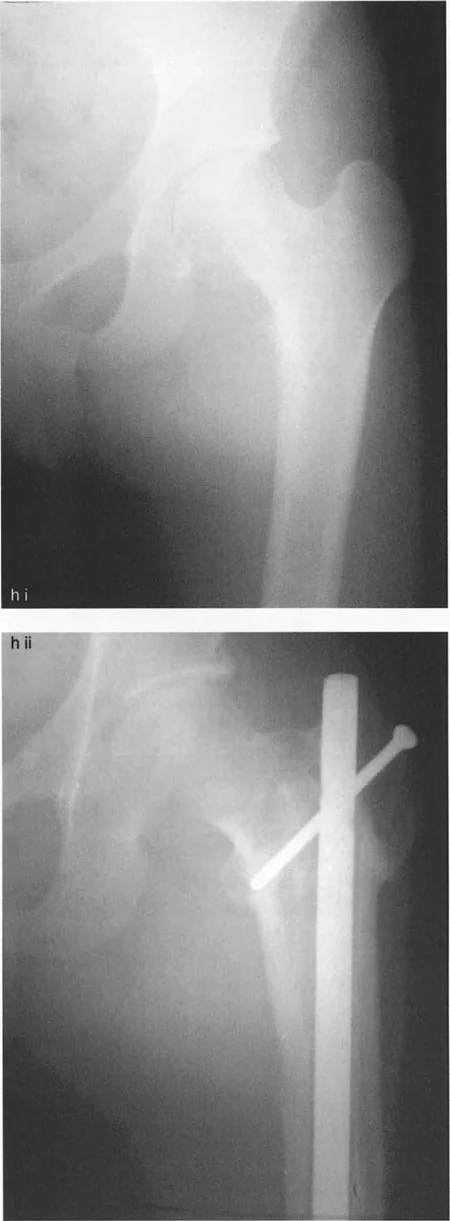

- تشوه فحجي مع دوران داخلي لعظم الفخذ القريب وخلع جزئي للورك: قد يتطلب هذا قطع عظم فاروسي مع إزاحة وسطية ونقل المدور الكبير للأسفل والجانب.

صور بالأشعة السينية لحالة فتاة تعاني من تشوه فحجي مع دوران داخلي وخلع جزئي، توضح التدخل الجراحي بقطع عظم فاروسي مع نقل المدور الكبير والتثبيت بمثبت خارجي، ثم النتيجة النهائية بعد التعافي.